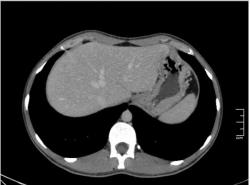

КТ печени. Наблюдения для размышления.

Уважаемые коллеги, особенно врачи КТ. Надеюсь что данная публикация окажется полезной для многих из Вас. Ниже представлены сканы печени; предлагаю Вам ознакомится с ними и высказать свое мнение. Пациент мужчина средних лет, специфичных жалоб не предъявляет.

Если Вы не против, я немного придержу продолжение данного наблюдения. Основная задача данной публикации не сам диагноз, а показать современные аспекты и особенности метода КТ, а также важность глубины и объёма знаний врачей радиологов которые занимаются КТ диагностикой.

Уважаемый v1tal! Огромная Вам благодарность; Вы назвали ключевое слово: фаза! Высказанная Вами мысль, это моя основная цель данной публикации. Постараюсь позже более детально объяснить почему. Представленные сканы выше, были выполнены на стандартной портальное фазе. А сейчас, я покажу сканы данного пациента выполненные на артериальной фазе :

Да Ola la, Вы абсолютно правы; это Фокальная Нодулярная Гиперплазия печени (FNH Focal Nodular Hyperplasia). Одна из немногих гиперваскулярных опухолей печени. Наверное некоторые коллеги спросят, и зачем было изначально публиковать портальную фазу, на которой «не видно» (хотя опухоль видна, пусть и не напрямую, и Nela это доказала); и только потом показывать сканы на артериальной фазе, на которой всё «красиво и показательно». Постараюсь объяснить.

За эти два года, в течении которых я познакомился с радиологическим русскоговорящим интернетом, я пришёл к определённым выводам. К сожалению, при наличии уже довольно неплохого парка современной аппаратуры в клиниках России и СНГ (у меня лично аппаратура намного скромнее по возможностям чем например у Nela или v1tal), ощущается огромный пробел в знаниях очень многих врачей, которые работают на этих аппаратах. И как следствие, врачи классические рентгенологи, отправляя пациентов на до-обследование в эти клиники, получая при этом неудовлетворительный результат проведённых исследований, начинают полагать (и имеют на это право), что зачем все эти «КТ и МРТ», если мы по своим стандартным рентгенологическим методикам получаем тот же результат (если иногда и не лучше-живой пример тому публикация vital с дивертикулом пищевода, где врач КТ написал диафрагмальную грыжу). И когда я читаю такие посты, мне становится очень обидно, хотя повторюсь, я уже пониманию причины такого мышления. Тем более что мало кто знает, что КТ и МРТ это не «статические методики», при которых взял пациента, положил на стол, дал контраст (как, куда, на какой скорости-мало кого волнует), сделал одну спираль/фазу, и до свиданья, «подавайте» следующего. Современные протоколы КТ и МРТ выработаны ПОД КАЖДЫЙ КОНКРЕТНЫЙ ДИАГНОЗ, иными словами, если мы подозреваем заболевание кишечника, и снимем пациента по протоколу разработанному для диагностики патологии печени или поджелудочной, то мы можем пропустить «всё на свете» в кишечнике, и при этом ничего не найти в печени или панкреас.